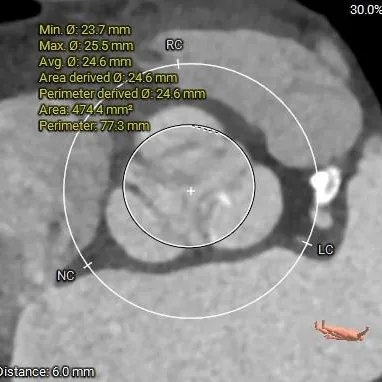

瓣上6mm

24.6mm